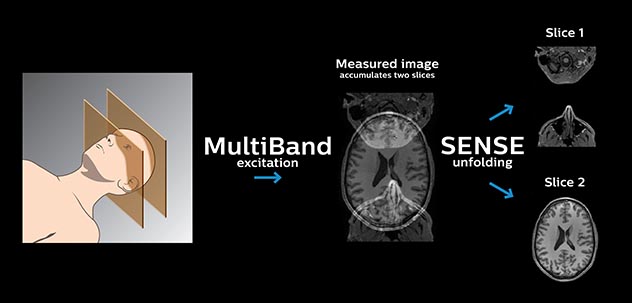

Resting state fMRI

Imaging was performed using Ingenia 3T CX with a 32ch dS Head coil, TR 1.6 sec, TE 35 ms, voxel size 3.1 x 3.1 x 3.1 mm, 46 slices and Multiband SENSE factor 2. Image provided by Dr. Gispert

Default mode network as discovered by resting state fMRI in one participant of the ALFA cohort [7]. rs-fMRI allows us to find networks of brain regions with highly correlated activity and sustaining distinct brain functions. The default mode network (in warm color scale) is active when the brain is focused on introspective thinking and has been shown to be altered in Alzheimer’s. Interestingly, brain areas of this network are known to show abnormal levels of one of the pathological hallmarks of Alzheimer’s (b-amyloid deposition) in preclinical stages. We want to better understand the alterations of these brain networks in preclinical stages of Alzheimer's and explore their potential use as biomarkers.